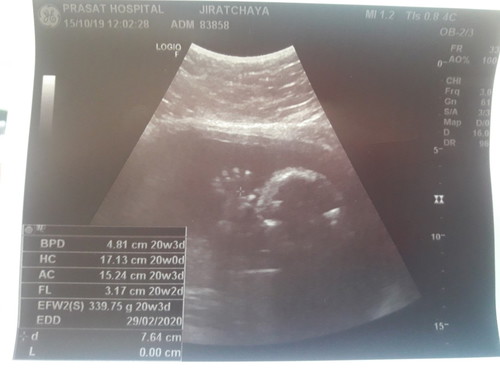

ความยาวของลูกดูตรงไหนค้ะช่วยดูให้หน่อย

หาตัวย่อ CRL ค่ะ คือความยาวของทารก BPD = การวัดความกว้างของศีรษะทารก HC = การวัดเส้นรอบวงศีรษะ FL = การวัดความยาวกระดูกต้นขา